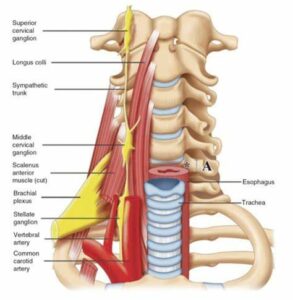

Nervo vago e arteria vertebrale

Il sistema occipito-atlanto-assiale coinvolge direttamente il nervo vago all’uscita del foro lacero posteriore ed è attraversato dall’arteria vertebrale prima che questa entri nel cranio tramite il forame magno. Uno squilibrio del sistema può recare quindi cervicalgie, vertigini, capogiri, sintomi gastro-intestinali, e altri sintomi neurovegetativi legati all’attività neurologica del nervo vago e dall’afflusso dell’arteria vertebrale

Ganglio cervicale superiore

Anteriormente alle masse trasverse di C2 sono presenti i gangli cervicali superiori. Questi gangli fanno parte della catena del sistema ortosimpatico e presentano anastomosi con il nervo vago, il glossofaringeo e l’ipoglosso. Oltre a questi collegamenti, dal ganglio diparte il nervo carotico interno che segue la carotide interna (funzione vaso motrice) e forma il plesso carotideo. Da questo plesso origina una radice del ganglio ciliare che si dirige verso il bulbo oculare. Sempre da questo ganglio origina il nervo carotico esterno, i rami faringei per il plesso faringeo e il nervo cardiaco superiore che partecipa alla formazione del plesso cardiaco. Inoltre sono stati scoperti anche nervi che si dirigono alle strutture dell’encefalo, influenzando funzioni intellettive come l’apprendimento, le onde cerebrali e la secrezione di ormoni come la melatonina. Per tutti questi collegamenti, una disfunzione della seconda vertebra cervicale quindi può influenzare la funzionalità di questi gangli generando vari tipi di sintomi tra ipertensione arteriosa, dolore all’occhio, difficoltà ad addormentarsi, rallentamento dell’apprendimento.